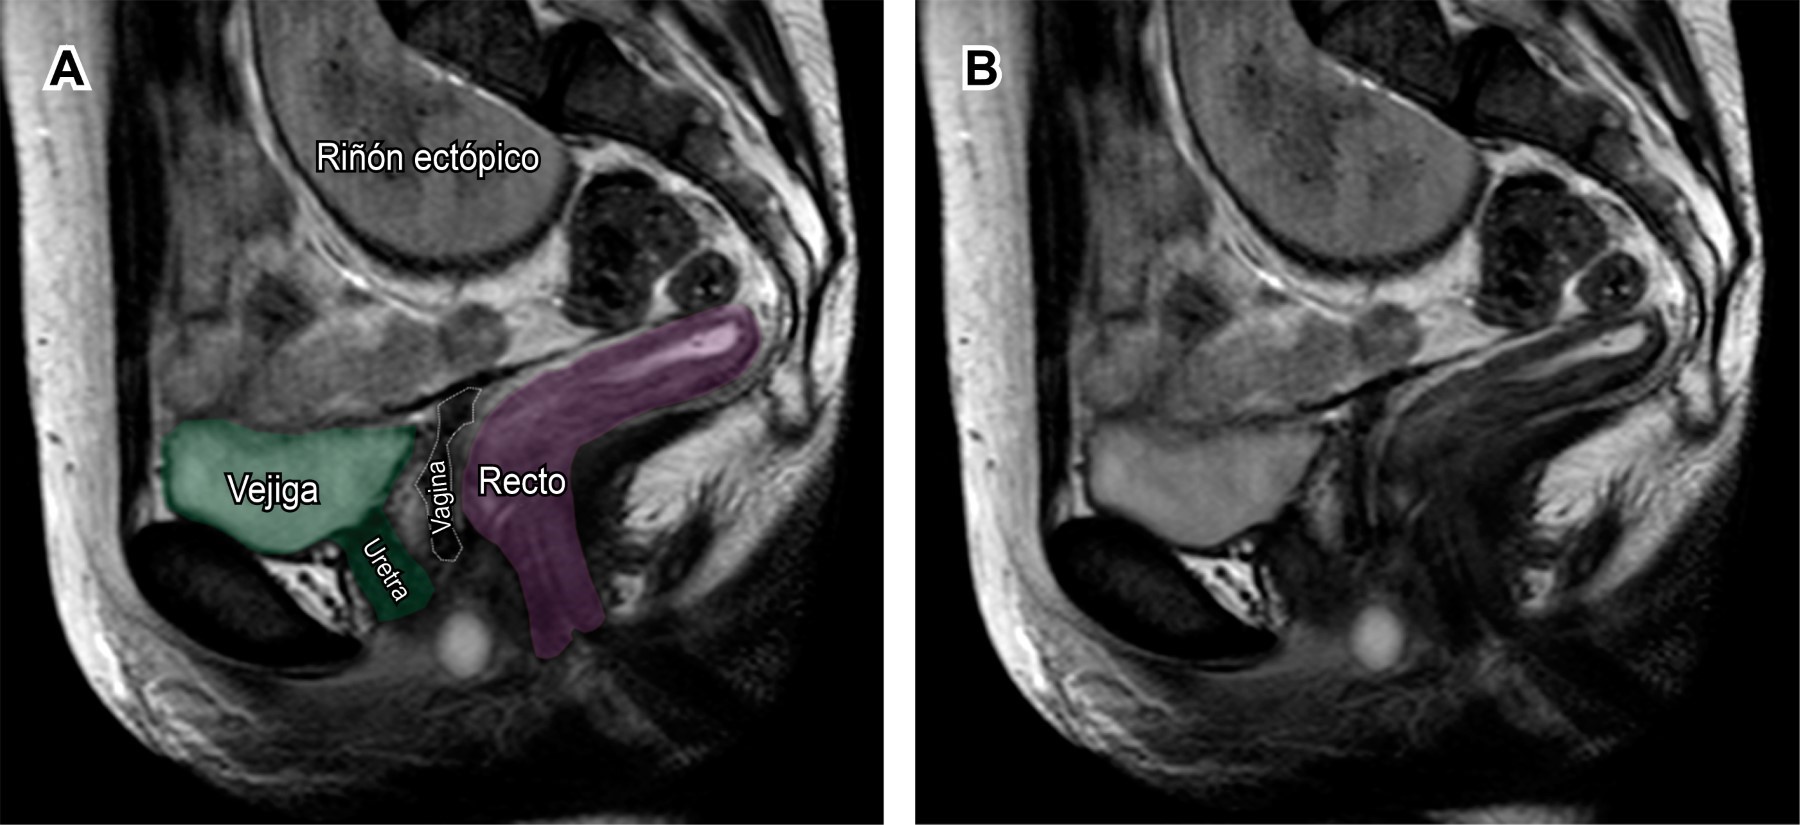

En el caso descrito se realizó un protocolo de resonancia magnética para valoración de útero, vagina y ovarios, observándose ausencia del útero y los dos tercios proximales de la vagina, con ovarios normales y riñón derecho ectópico de localización pélvica (Figuras 1 y 2), por lo que se encasilló en el grupo I de las malformaciones mu?llerianas de la American Fertility Society y específicamente como síndrome de Mayer-Rokitansky-Küster-Hauser tipo II (MURCS).

Figura 1

Figura 2